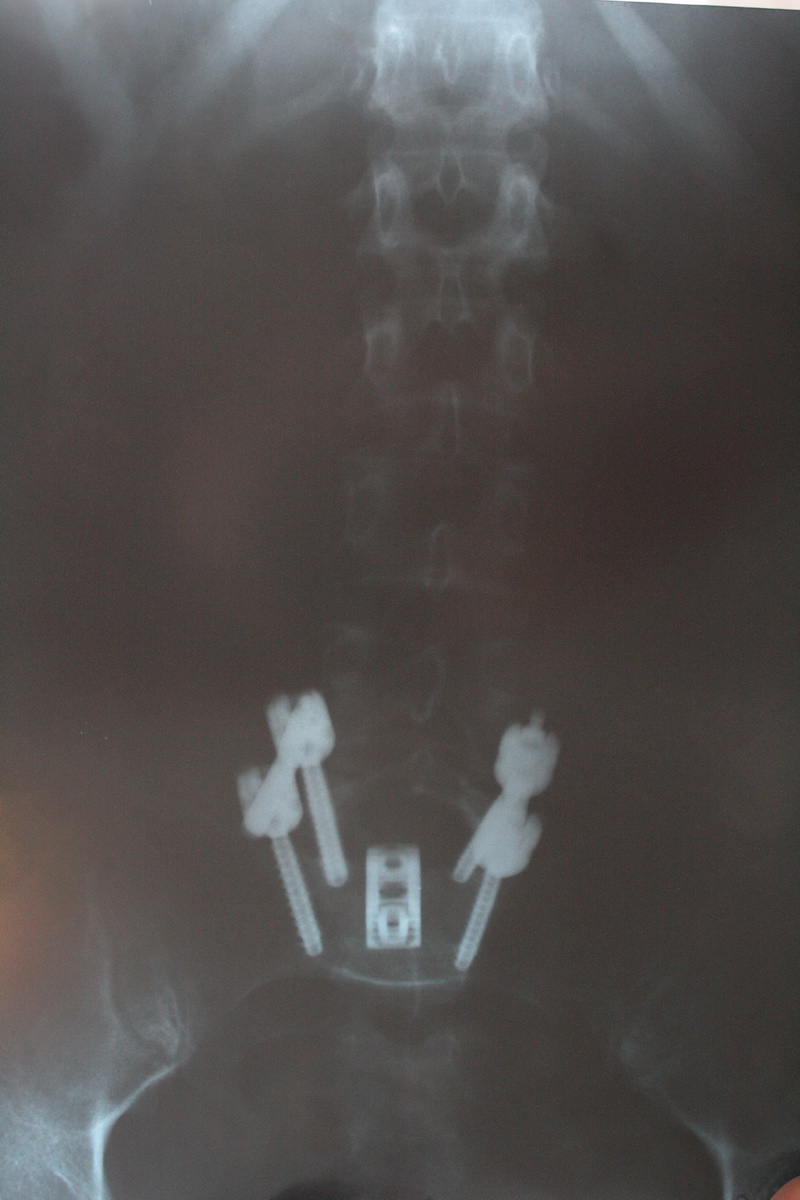

А что у вас с поясничным отделом?Сейчас так, как на фото.

А изначально был спондилолистез истмический нестабильный. Зафиксировали.

Плюс - спондилоартроз, протрузии, как у многих в моем возрасте.